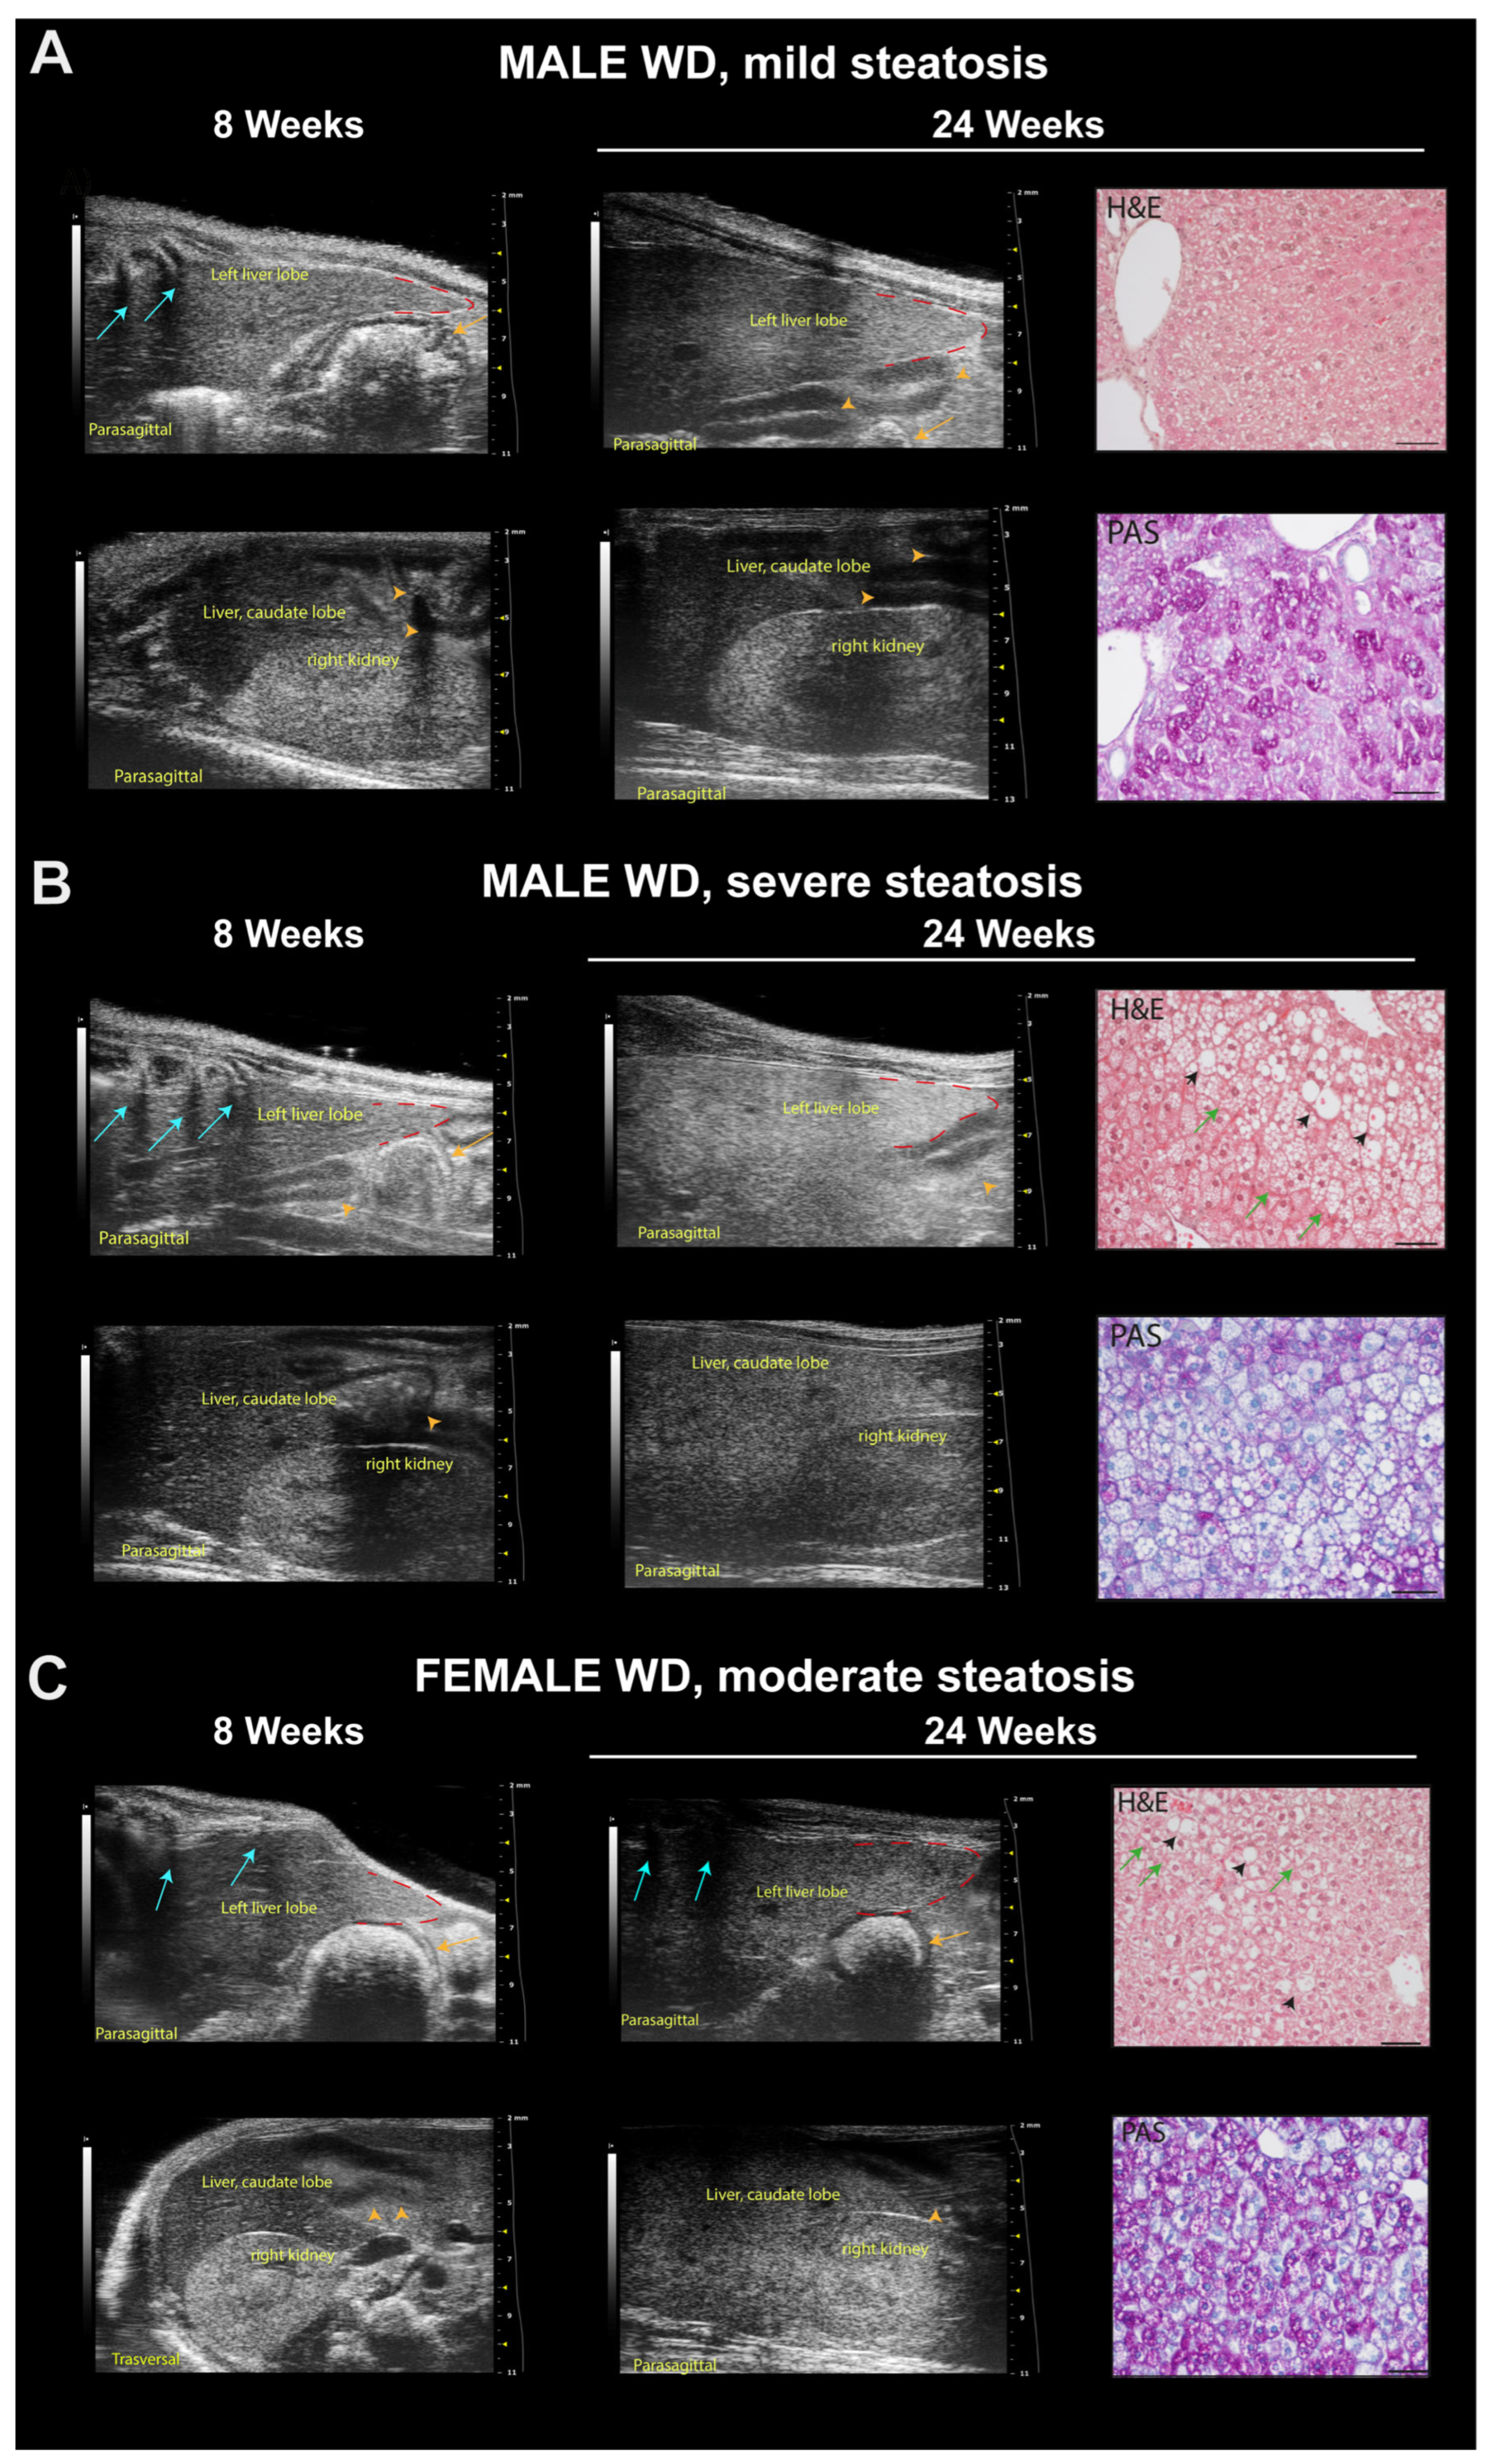

3.6. WD Causes Progressive Structural and Functional Changes in the Heart, Liver, and Kidney of C57Bl/6J Mice That Can Be Detected Early and Monitored In Vivo by HFUS

3.7. WD Induces Histological Changes in the Liver and Kidney of C57Bl/6J Mice